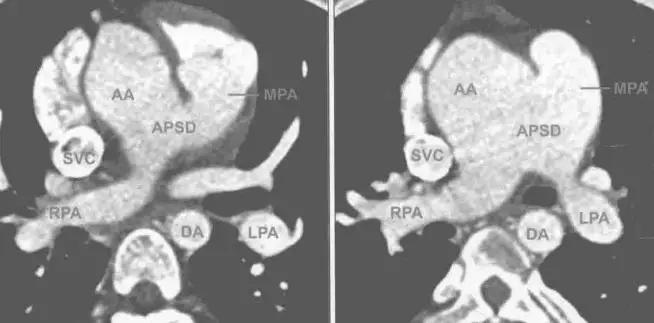

5.CTMR表现

I型:可见缺损紧邻半月瓣的上部层面,升主动脉左后壁与肺动脉主干的右前壁相连通,二者之间有血流信号或造影剂通过

II型:缺损位于升主动脉的远端,此型易与窗型动脉导管未闭相混淆,当PDA位于降主动脉和肺动脉之间,在图像上表现为缺损的前方是肺动脉,后方是(降)主动脉,而APSD恰好相反,APSD的右前方是升主动脉,而左后方是主肺动脉。

III型:缺损较大,累及升主动脉的全部或大 部,此型易于共同动脉干相混淆,但是APSD有两组半月瓣分别连接主动脉与左心室和肺动脉与右心室,而共同动脉千只有一组大的半月瓣